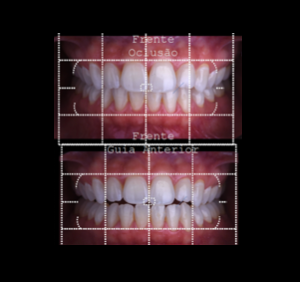

Protocolo Fotográfico

Podem ser feitas fotos artísticas, extra-bucal e/ou intra-bucal